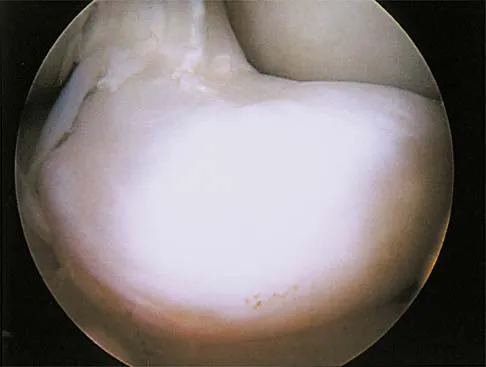

A 29-year-old woman who underwent an anterior cruciate ligament (ACL) reconstruction 6 months ago now reports difficulty achieving full knee extension, and physical therapy fails to provide relief. The knee is stable on ligament testing. Figure 3 shows the findings at a repeat arthroscopy. Treatment should now include

Explanation

The patient has a cyclops lesion. This is a nodule of fibroproliferative tissue that originates from either drilling debris from the tibial tunnel or remnants of the ACL stump; more rarely it is the result of broken graft fibers. The treatment of choice is excision of the nodule and, if needed, additional notchplasty. Marked improvements in function and symptoms have been noted after removal of the extension block and resumption of a rehabilitation program. Delince P, Krallis P, Descamps PY, et al: Different aspects of the cyclops lesion following anterior cruciate ligament reconstruction: A multifactorial etiopathogenesis. Arthroscopy 1998;14:869-876.